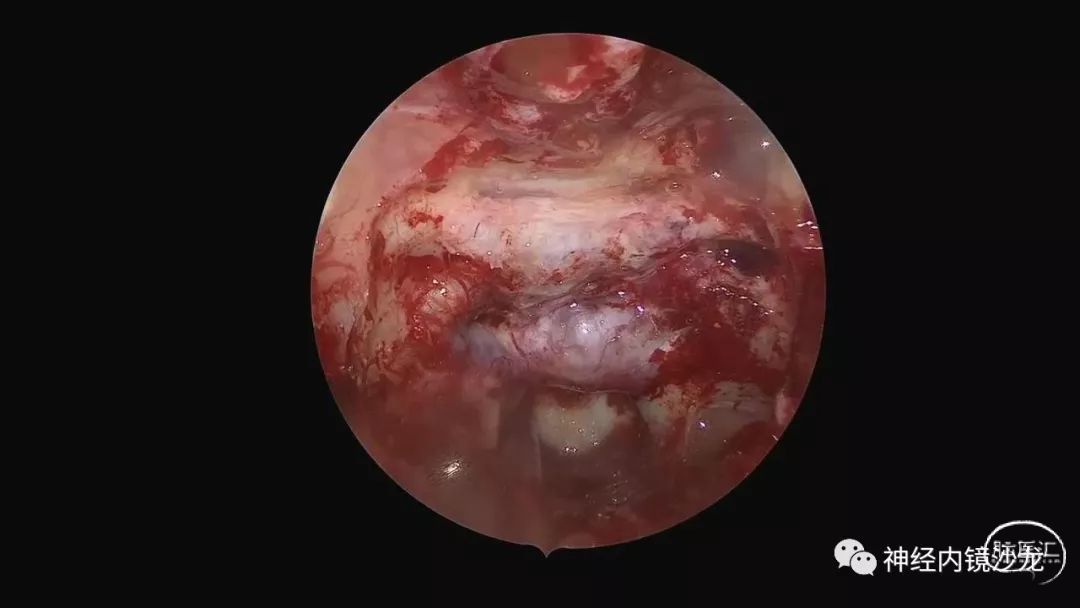

精彩图表

从事神经外科十余年,擅长神经外科肿瘤诊治,尤其是神经内镜微创手术治疗垂体瘤、颅咽管瘤、脑膜瘤等颅底肿瘤